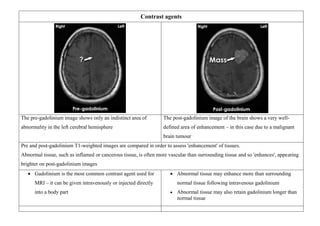

Contrast agents

The pre-gadolinium image shows only an indistinct area of

abnormality in the left cerebral hemisphere

The post-gadolinium image of the brain shows a very well-

defined area of enhancement – in this case due to a malignant

brain tumour

Pre and post-gadolinium T1-weighted images are compared in order to assess 'enhancement' of tissues.

Abnormal tissue, such as inflamed or cancerous tissue, is often more vascular than surrounding tissue and so 'enhances', appearing

brighter on post-gadolinium images

 Gadolinium is the most common contrast agent used for

MRI – it can be given intravenously or injected directly

into a body part

 Abnormal tissue may enhance more than surrounding

normal tissue following intravenous gadolinium

 Abnormal tissue may also retain gadolinium longer than

normal tissue